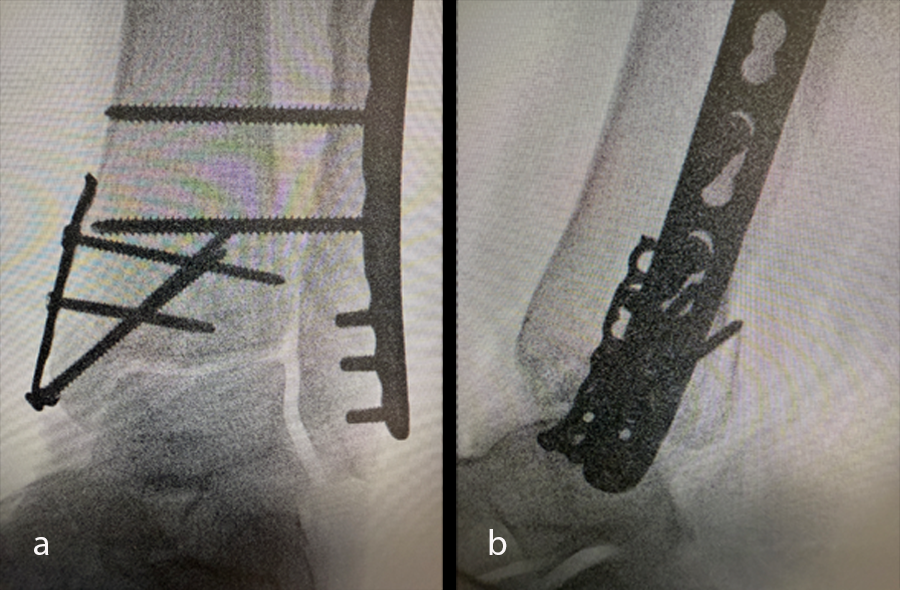

Once the soft-tissue swelling had reduced sufficiently, the patient underwent open reduction and internal fixation (ORIF) surgery, with the VOLT™ Mini Fragment hook plate medially and the Small Fragment metaphyseal plate laterally. The syndesmosis was addressed with 4.0 mm screws (Fig 34). The surgery was uneventful and performed on an ambulatory basis.

At the 6-week postoperative follow-up, the patient reported no pain and was advised to start progressive weight bearing with formal physiotherapy, and progressed from the CAM boot to a cushioned heel, rocker bottom shoe. X-rays taken at this time (Fig 35) showed good position of hardware and the fracture with signs of early healing.